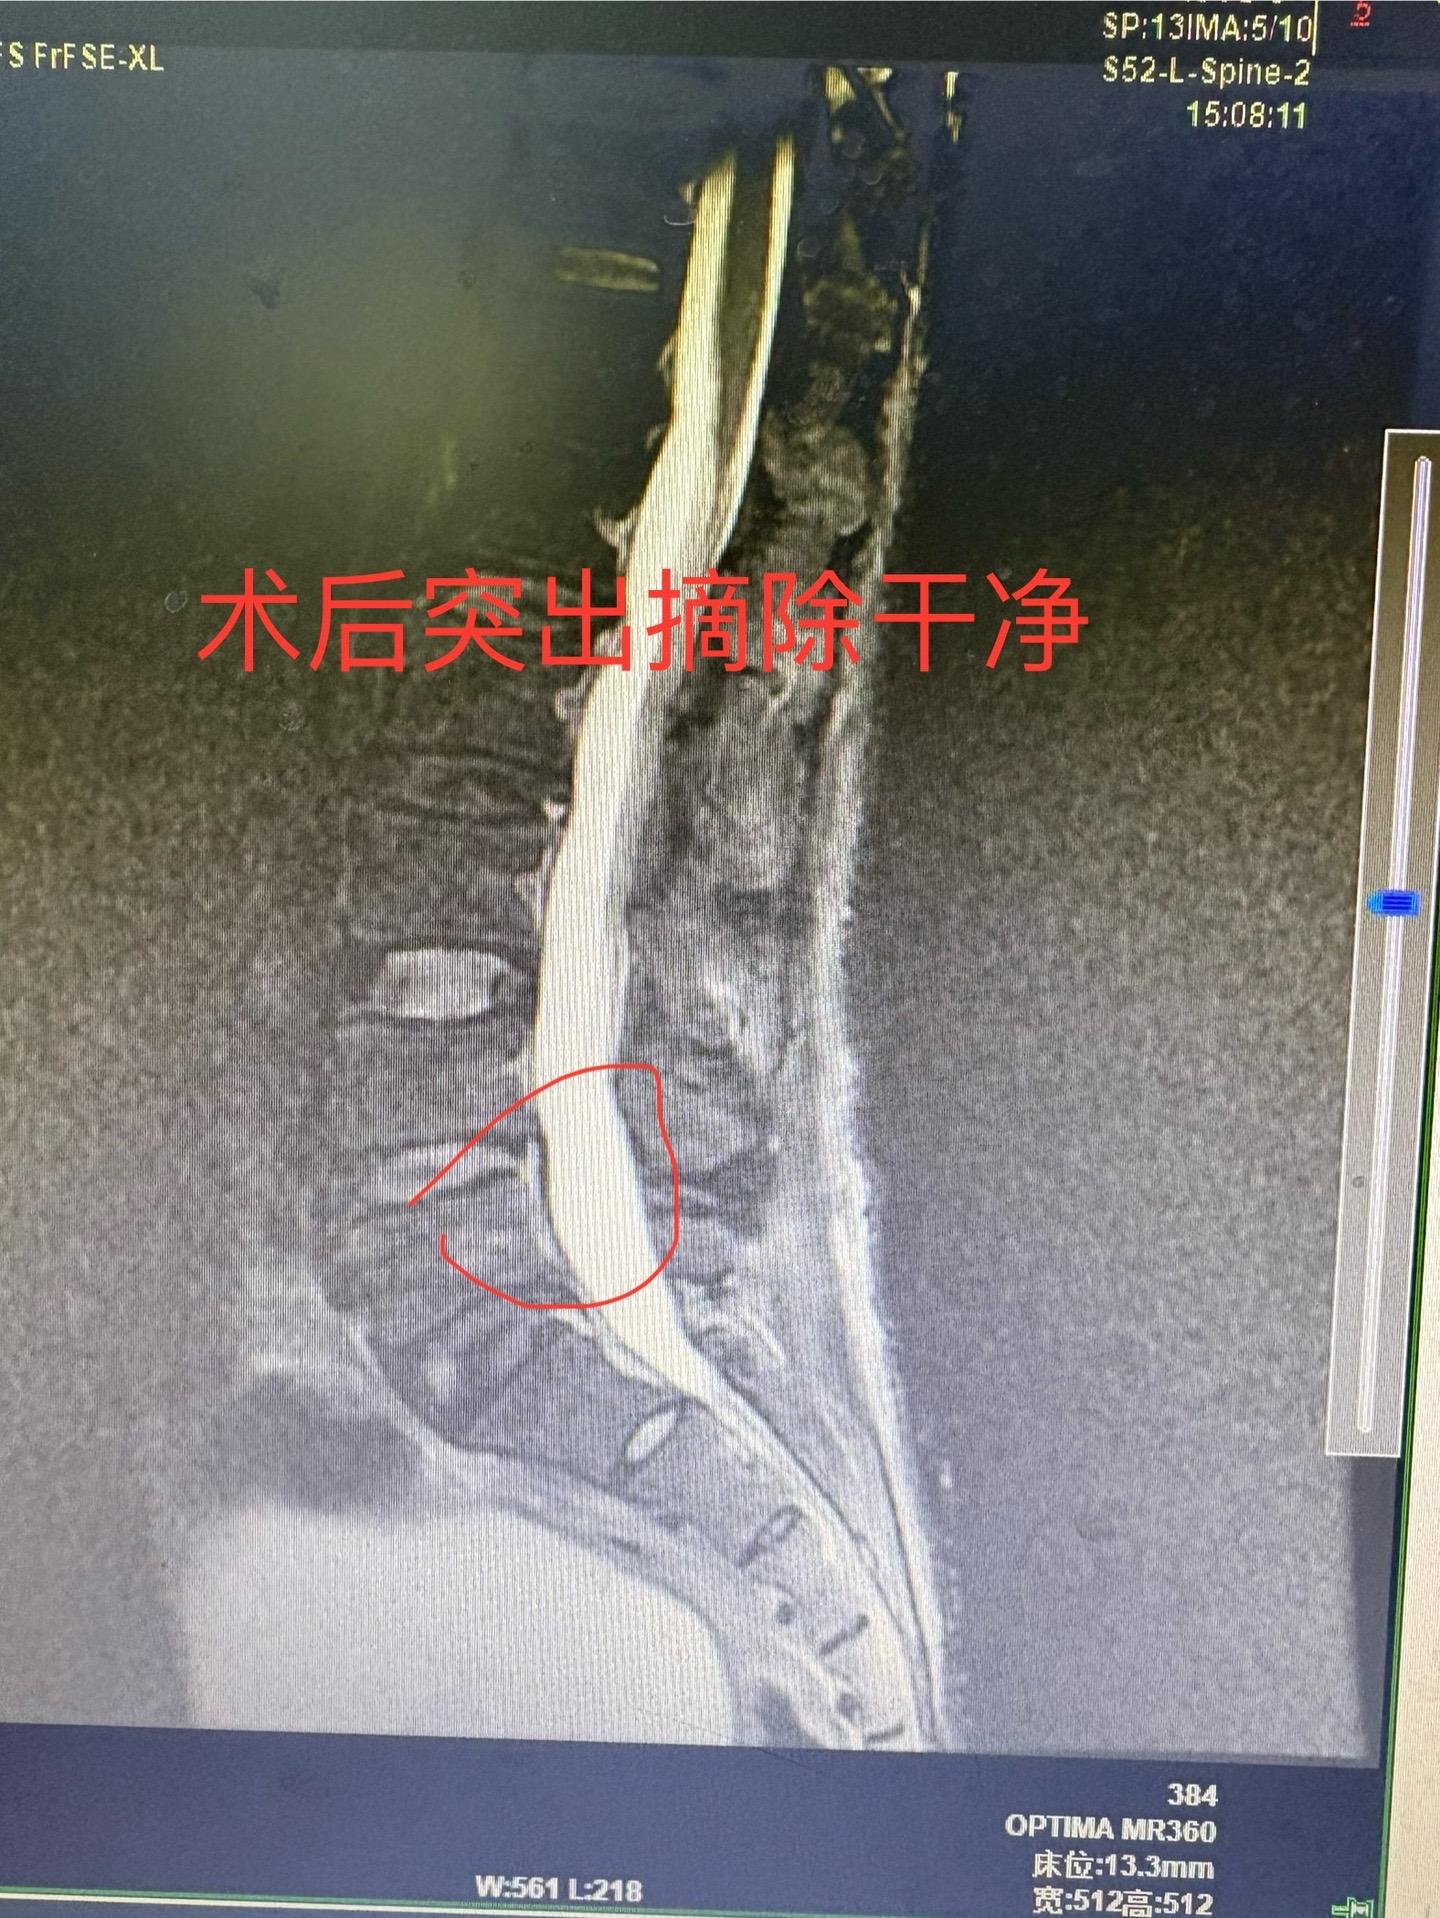

脱出的腰椎间盘,选择局麻的内镜手术也是可以的,但是也有可能会残留,需要...